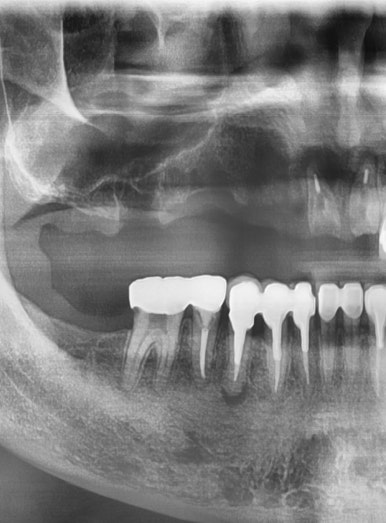

원장님이 해외에서 공부중일 때 다른 치과에서 임플란트를 여러개 하셨는데요

빨간색 화살표로 표시한 부분의 인플란트 주변 뼈가 녹아서 임플란트가 흔들리는 상태였습니다.

화살표 부위 치아 외에 뒤에 치아가 원래 하나더 있어야 개수가 맞기 때문에

임플란트 2개를 더 있어야하는데

아마 고난도의 상악동 거상술이 필요해서 다른 치과에서 임플란트를 뼈가 그나마 있는 화살표 부분에만 심었던 것 같습니다.